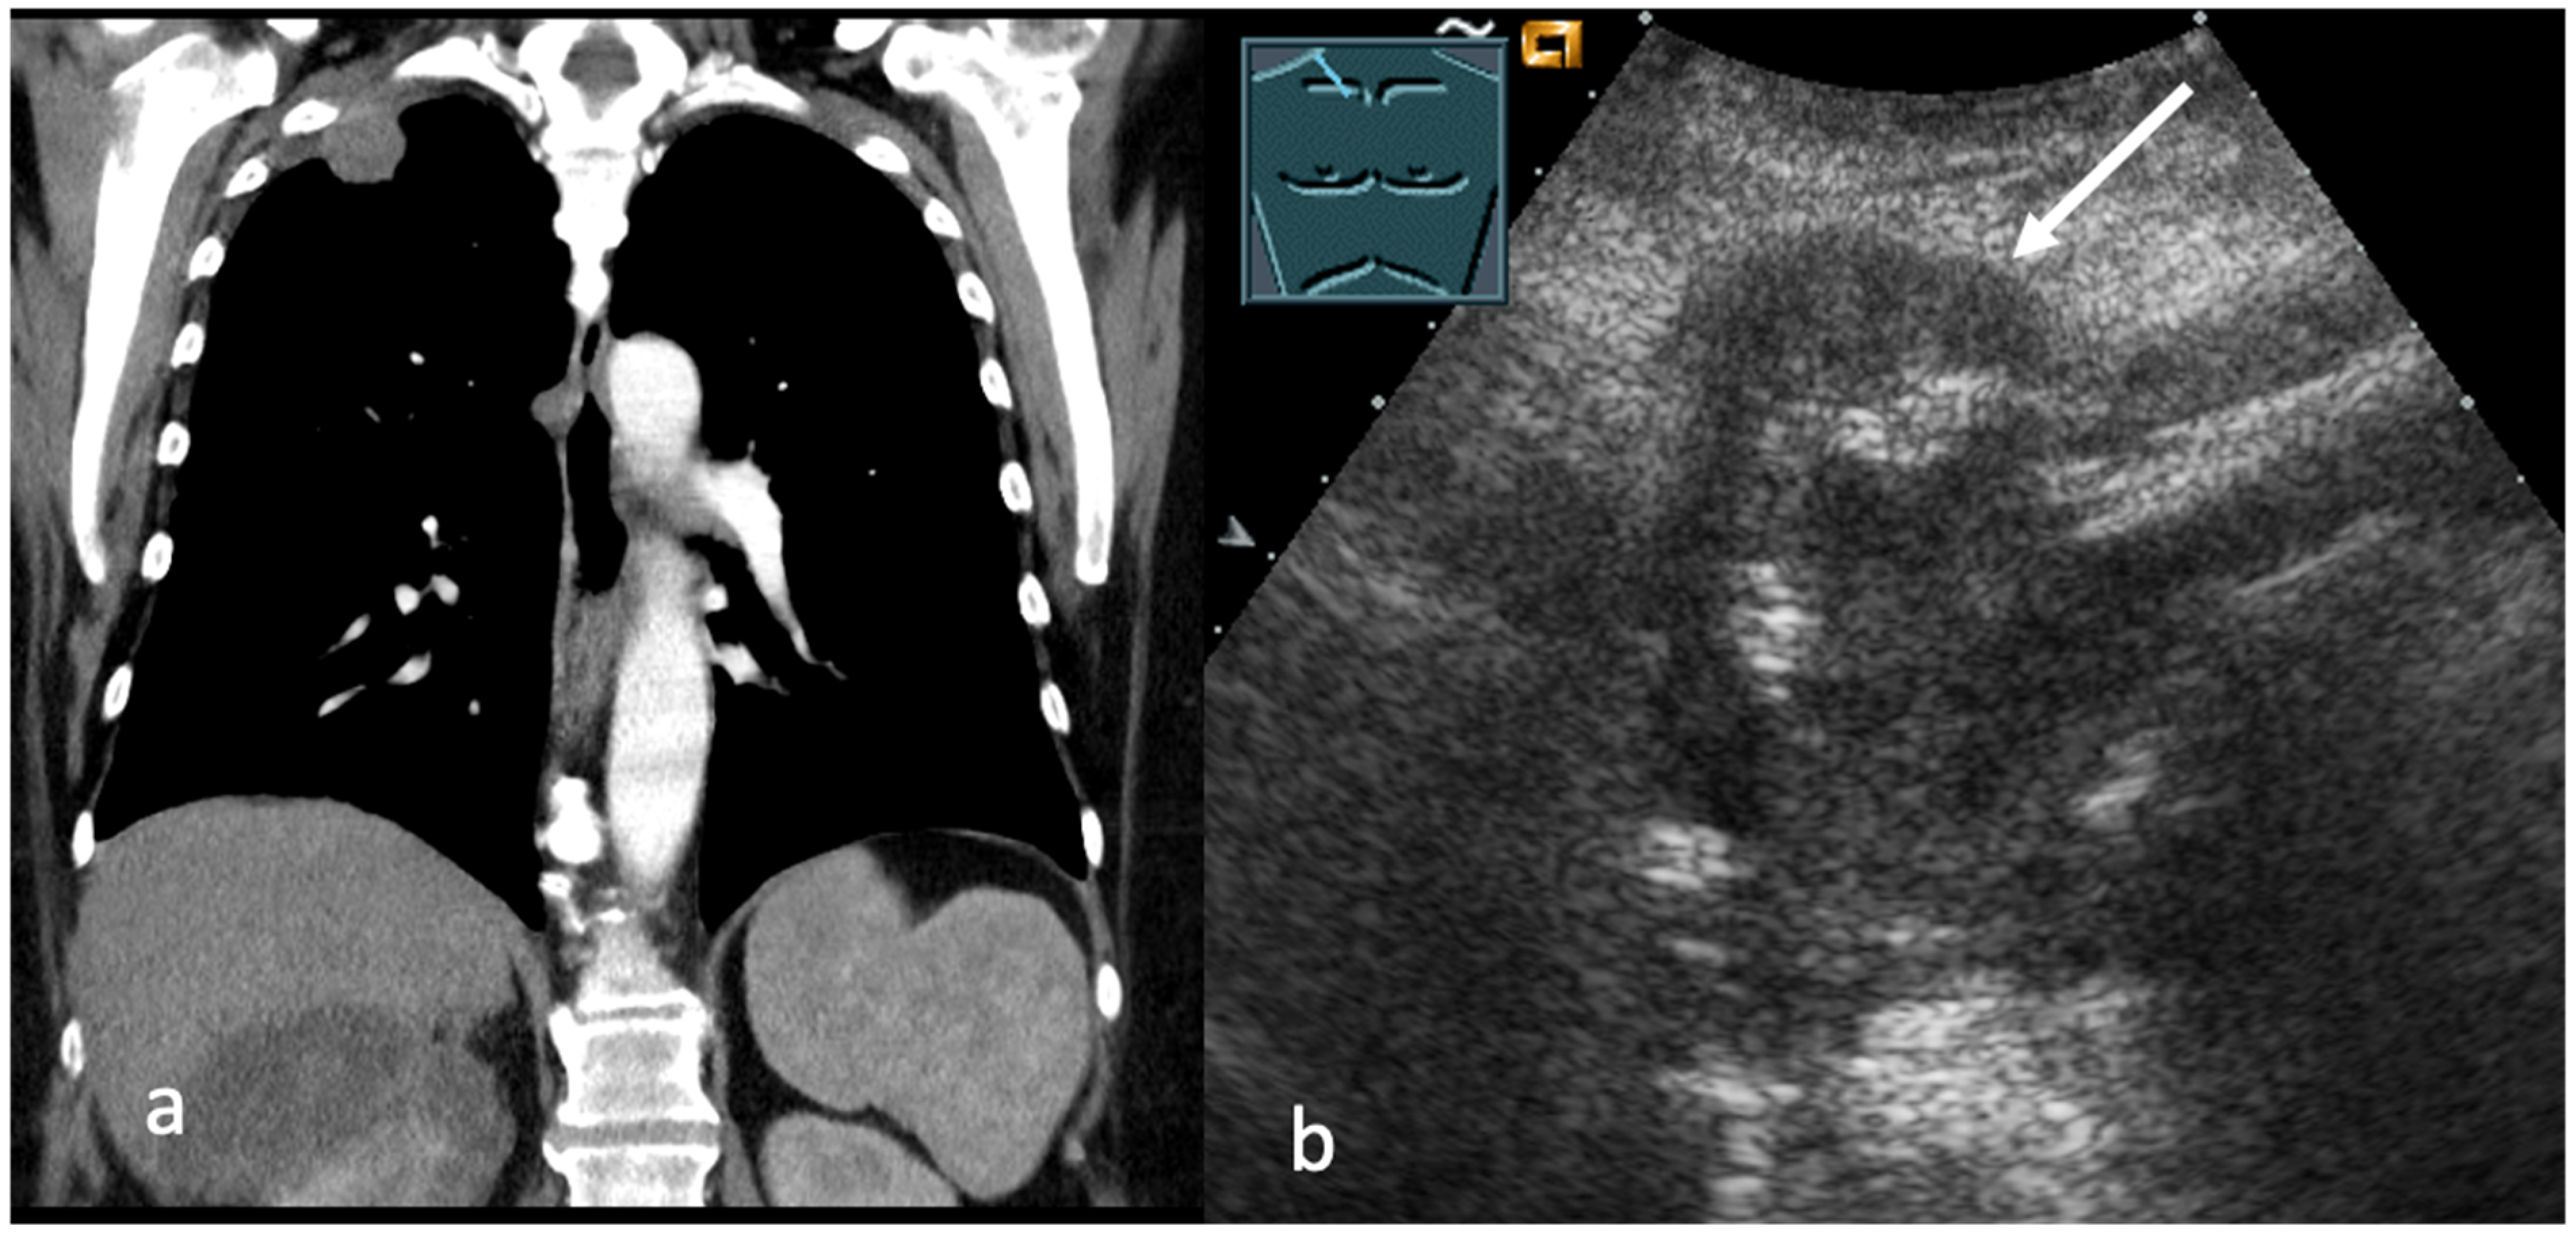

5. Transcutaneous Ultrasound in the Evaluation Distant Metastasis

- Yousefifard, M.; Baikpour, M.; Ghelichkhani, P.; Asady, H.; Shahsavari Nia, K.; Moghadas Jafari, A.; Hosseini, M.; Safari, S. Screening Performance Characteristic of Ultrasonography and Radiography in Detection of Pleural Effusion; a Meta-Analysis. Emergency 2016, 4, 1–10. [Google Scholar]

- Mathis, G. Use of lung and pleural ultrasonography in emergency and intensive care medicine. Med. Klin. Intensivmed. Notfmed. 2019, 114, 504–508. [Google Scholar] [CrossRef]

- Yang, P.C.; Luh, K.T.; Chang, D.B.; Wu, H.D.; Yu, C.J.; Kuo, S.H. Value of sonography in determining the nature of pleural effusion: Analysis of 320 cases. AJR Am. J. Roentgenol. 1992, 159, 29–33. [Google Scholar] [CrossRef]

- Safai Zadeh, E.; Weide, J.; Dietrich, C.F.; Trenker, C.; Koczulla, A.R.; Görg, C. Diagnostic Accuracy of B-Mode- and Contrast-Enhanced Ultrasound in Differentiating Malignant from Benign Pleural Effusions. Diagnostics 2021, 11, 1293. [Google Scholar] [CrossRef]

- Findeisen, H.; Görg, C.; Hartbrich, R.; Dietrich, C.F.; Görg, K.; Trenker, C.; Safai Zadeh, E. Contrast-enhanced ultrasound is helpful for differentiating benign from malignant parietal pleural lesions. J. Clin. Ultrasound 2022, 50, 90–98. [Google Scholar] [CrossRef] [PubMed]